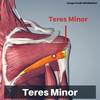

Label this image

what are the intrinsic shoulder muscles?

- teres minor